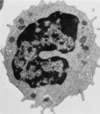

ID the cell

Proerythroblast